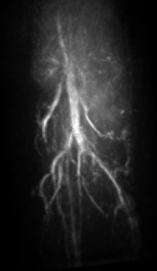

V.3 Experimental results

The maximum intensity projection (MIP) of the 3D mouse images reconstructed by use of the GPU-based implementations reveal the mouse body vasculature as shown in Fig. 7. Images reconstructed by use of both the PLS-Int and the PLS-Sph algorithms appear to have cleaner background than do the images reconstructed by use of the FBP algorithm from the same amount of data. All images reconstructed by iterative algorithms were obtained by 202020-iterations starting with uniform zeros as the initial guess. The PLS-Int algorithm took approximately a half day and 222 days to process the “quarter data” and the “full data” respectively. The PLS-Sph algorithm took approximately one day and 444 days to process the “quarter data” and the “full data” respectively. Alternatively, if the CPU-based implementations were utilized, the PLS-Int algorithm would take an estimated 686868 days and 277277277 days to process the “quarter data” and the “full data” respectively. The PLS-Sph algorithm would take an estimated 275275275 days and 1,10011001,100 days to process the “quarter data” and the “full data” respectively.